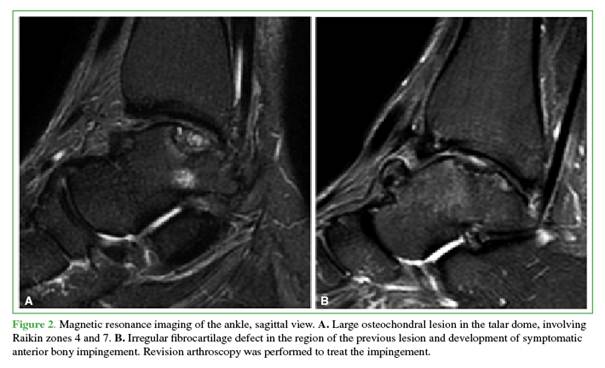

Only one patient required revision surgery within the 2-year follow-up period. At 18 months postoperatively, he developed anterior impingement-related pain and underwent a repeat anterior ankle arthroscopy for impingement resection and removal of an intra-articular loose body (Figure 2).

Nine of the 13 patients were unable to engage in physical activity prior to surgery due to pain during exertion. Of these, 6 resumed and maintained physical activity 2 years postoperatively, while 3 continued to experience pain or discomfort during activity. The 4 patients who were active preoperatively remained active after surgery.